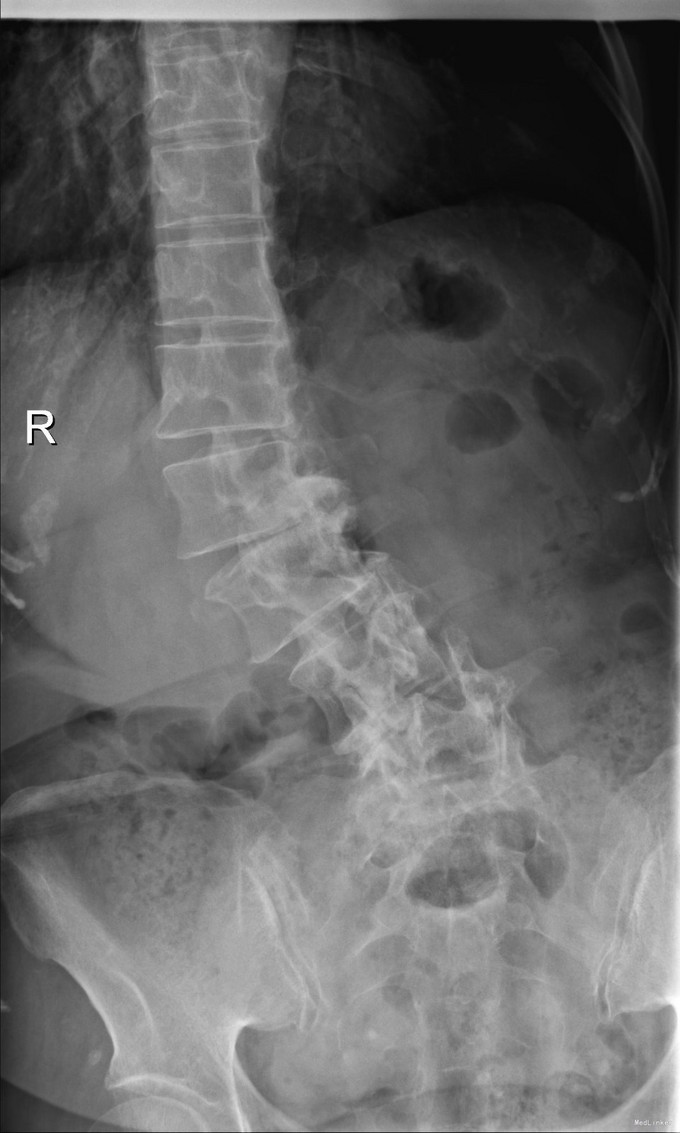

主诉:右下肢麻木11年,腰部酸痛无力 现病史:女性患者,65岁,患者于11年前无明显诱因下出现右下肢麻木,自大腿至右踝部,站立位加重。未予重视,后期出现腰臀部僵硬,弓背僵硬无力,自主行走距离不足200米,曾于06年经X线平片及MRI检查:腰椎椎管狭窄伴有腰椎滑脱,椎间盘突出等。

查体:侧弯畸形,右臀部及右下肢麻木疼痛,腰部活动受限,难以站立。右侧支腿抬高试验60°。双下肢肌力肌张力可。 辅助检查:平片:腰椎侧弯,椎体滑脱,曲度后凸 磁共振:L2-3,L4-5,L5-S1腰椎椎管狭窄,l2-3L3-4L4-5L5-S1腰椎间盘突出,腰椎退变

诊断: 腰椎侧弯,腰椎间盘突出 治疗:1期微创侧路椎体融合术+2期 微创后路经皮内固定术